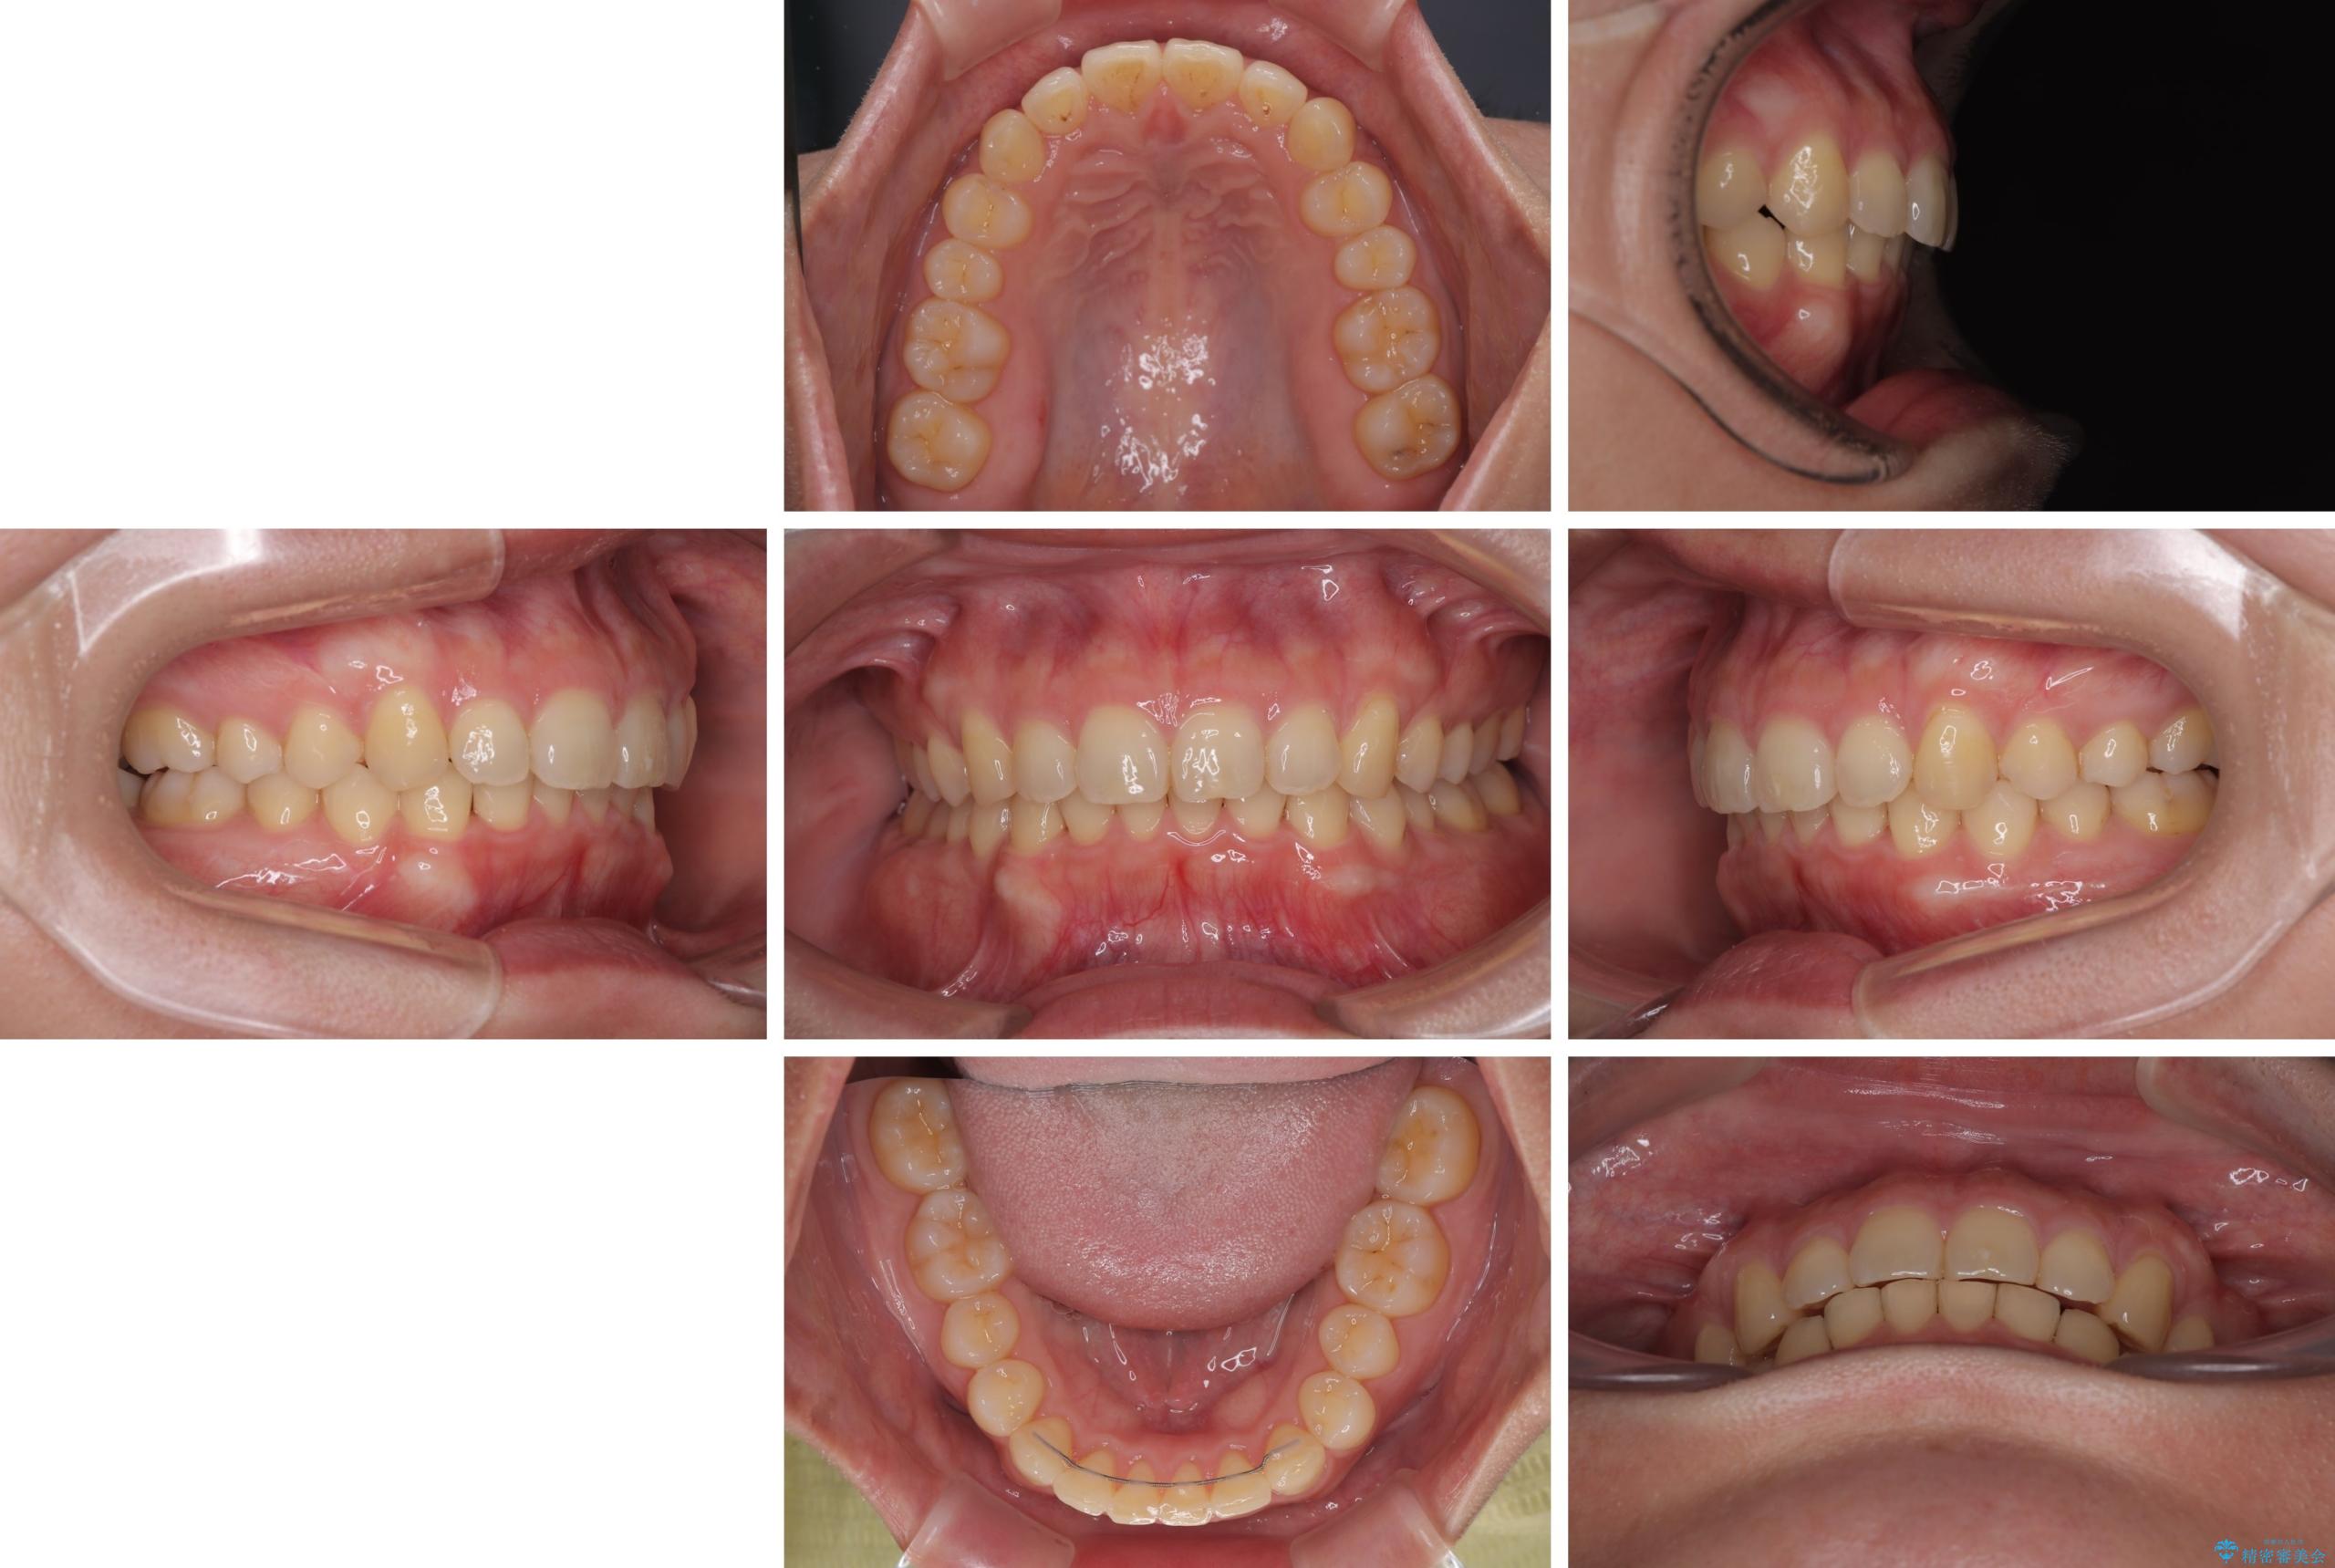

隠れた前歯が気になる ディープバイトのワイヤー矯正治療

- 下顎前歯が完全に隠れてしまっていることを気にして来院された患者様です。

下顎の臼歯が手前に傾斜していることで咬み合わせが深くなってしまい、下顎前歯が見えないほどに上顎前歯が覆い被さっている状態でした。

咬合力が強いことと、マウスピースを長時間装着する自信がないとのことで、ワイヤー装置にて矯正治療を行うこととしました。

下顎臼歯を起き上がらせるためにユーティリティーアーチを使用し、一気に深い咬み合わせを改善することができました。